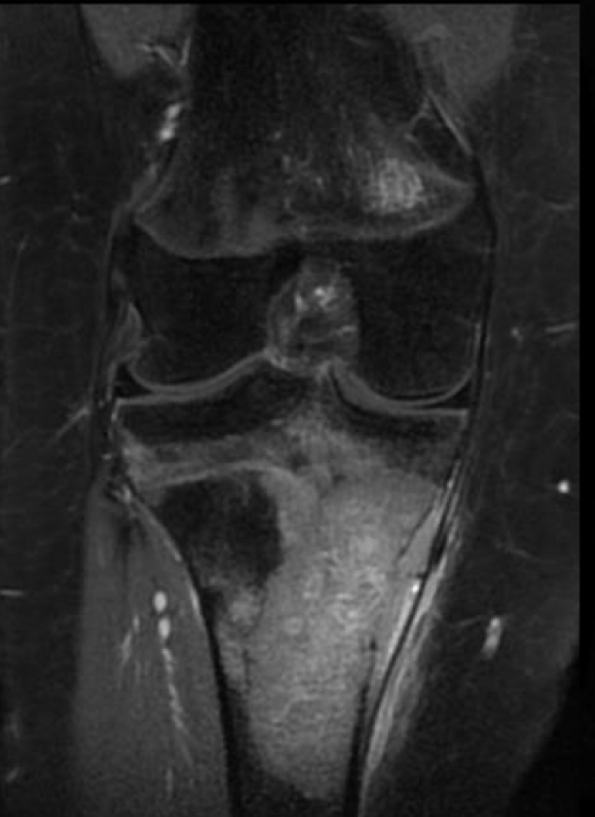

Q se ve y para q sirve rm

estadificacion

Determinar conservacion de extremidad

Extension intraosea y a tejido blando

Contraste

13

Q tiene

Osteosarcoma y FX en condilo lat